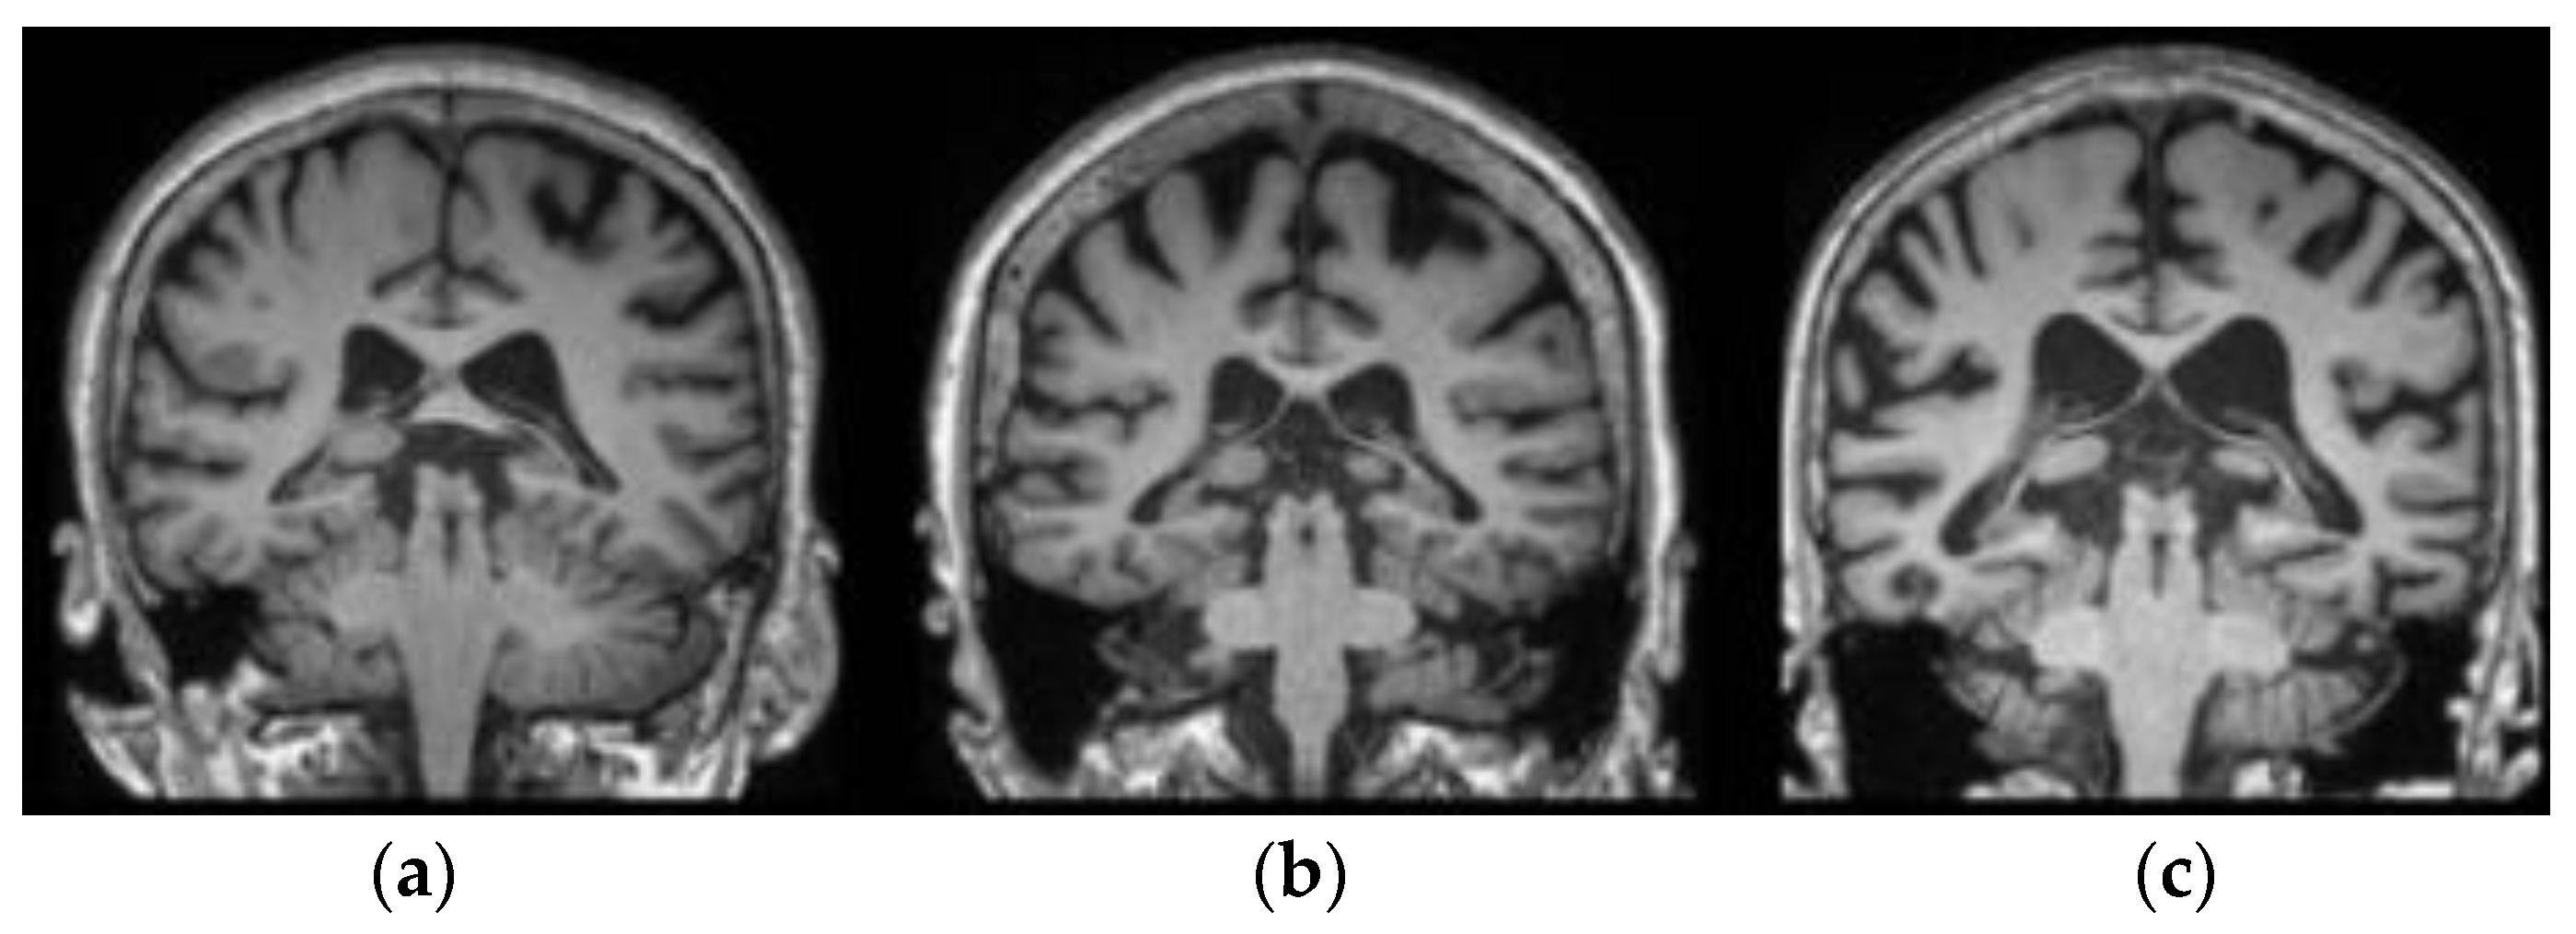

The proposed fuzzy-based superpixel-clustering algorithm and the MGTO-CapsNet model performance was tested on the ADNI, real time, and AIBL datasets. The ADNI dataset comprises 1662 sMRI images; here, the individuals are categorized into three types, including normal control (NC), AD, and mild cognitive impairment (MCI) [35]. The goal of ADNI is to create biochemical, genetic, imaging, and clinical biomarkers for the early identification and monitoring of AD. The historic public–private cooperation, which was established more than ten years ago, has significantly advanced AD research by facilitating the exchange of data amongst researchers worldwide (https://adni.loni.usc.edu/data-samples/) accessed on 14 November 2023. Furthermore, the AIBL dataset (https://aibl.csiro.au) accessed on 21 November 2023 consists of 496 sMRI images, and the individuals are categorized into three types, including 17 progressive MCI (pMCI), 93 stable MCI (sMCI), and 307 NC [36] subjects. Additionally, the real-time dataset was acquired from Rajiv Gandhi Government General Hospital (Chennai), and it comprises 200 sMRI images belonging to three classes (NC, AD, and MCI). The acquired sample sMRI images from the ADNI dataset (a), including the real-time dataset (b), and AIBL dataset (c) are visually presented in Figure 2.

Figure 2. Acquired sample sMRI images: (a) ADNI dataset, (b) real-time dataset, and (c) AIBL dataset.